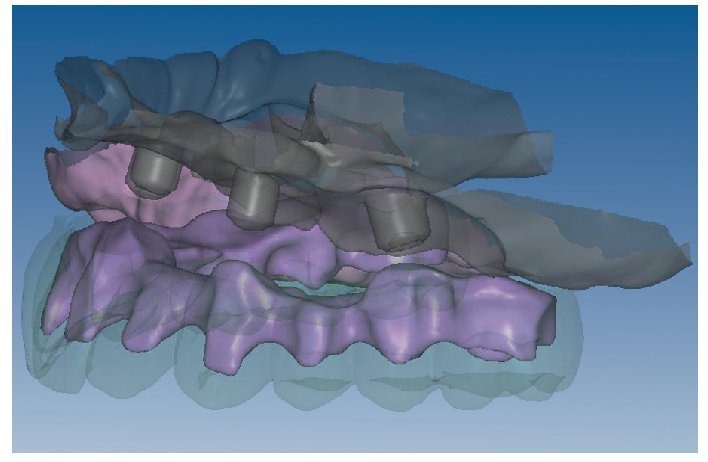

Mediante el uso de un escáner óptico de luz estructurada, los protocolos CAD registran los primeros datos relativos al modelo maestro con las correspondientes posiciones de implante (figs. 87 y 92). En el siguiente paso tiene lugar la digitalización de la planificación, previamente realizada en cera de escaneo matificada, de la restauración definitiva (figs. 88, 90 y 93). La subsiguiente conciliación de los datos mediante el uso del software de diseño dental permite al protésico planificar virtualmente el resto del procedimiento (figs. 89 y 91, 94 a 96) a partir del diseño de las estructuras (figs. 97 y 98).

Fig. 92. Imagen CAD del modelo maestro del maxilar inferior.

Fig. 93. Imagen CAD de la planificación definitiva para el maxilar inferior.

Figs. 94 a 95. Planificación CAD de la estructura del maxilar inferior, en representación lingual y vestibular.

Figs. 96 a 98. El diseño definitivo de la estructura del maxilar inferior, desde distintas perspectivas.